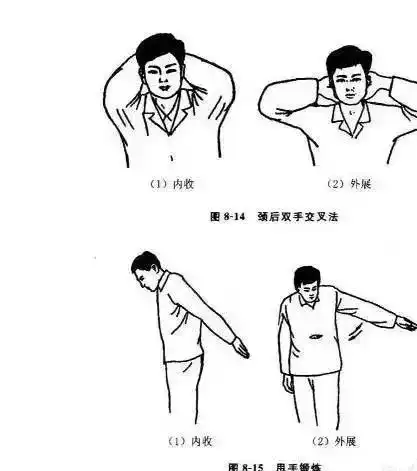

脊柱侧弯最全的康复训练方案

脊柱侧弯纠正大法多图详解,赶紧转走

体检发现脊柱有侧弯,该如何改善